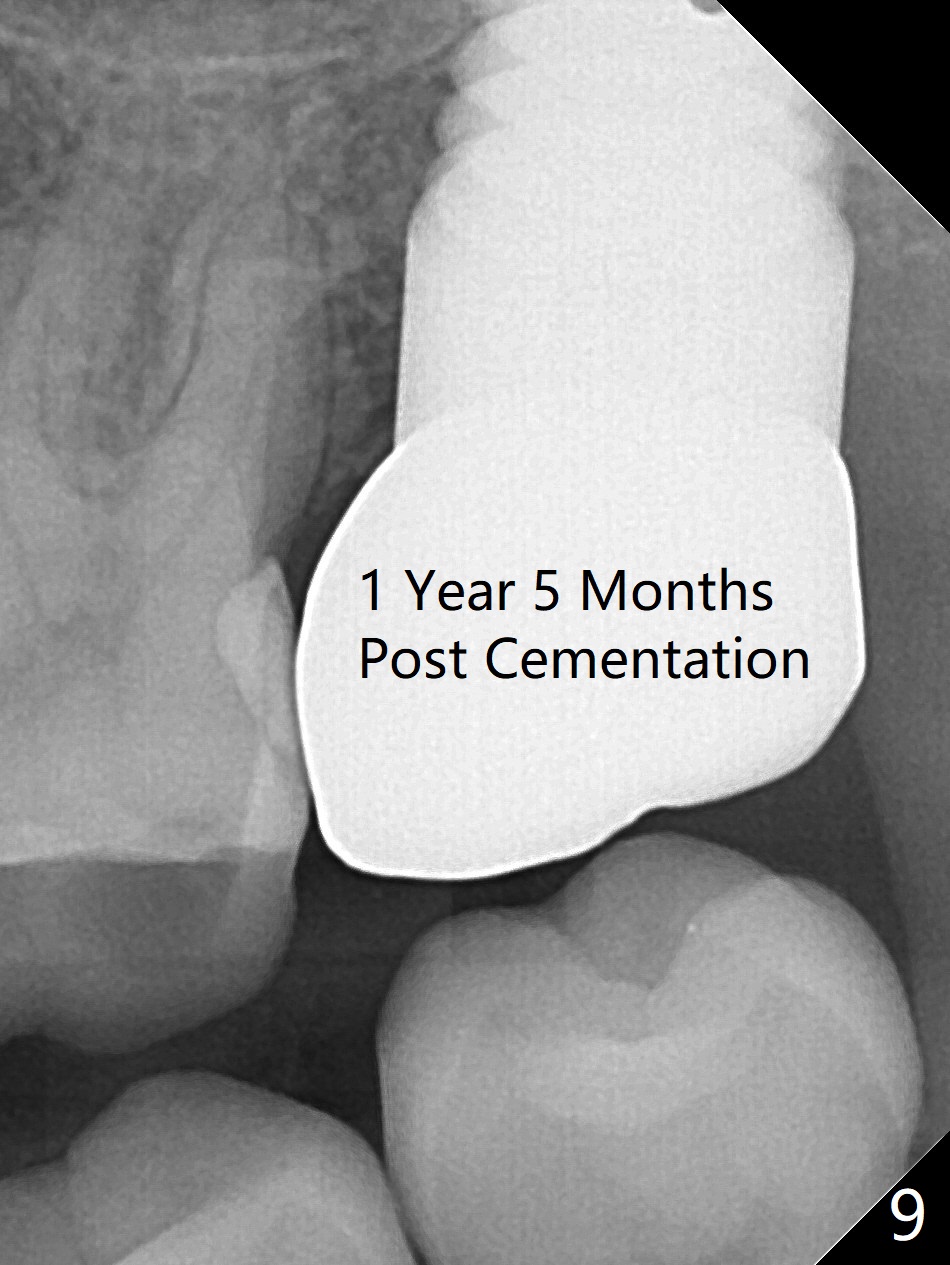

A 56-year-old woman has sign of periimplantitis 2 years 9 months post cementation. After incision, the 5.5x13 mm bone-level implant is ~ 3 mm inferior to the buccal crest. The implant is removed with 7/6 mm trephine bur, elevator and implant driver. The sinus membrane perforates. A 8x17 mm tap achieves stability (Fig.1), but the peripheral bone seems to be thin. Although a 7x14 mm tissue-level implant has stability, it is placed too deep (Fig.2). Following insertion of a piece of Osteogen plug for sinus membrane repair, a 8x14 mm implant is placed with >40 Ncm with allograft placed around the unpolished portion of the implant (Fig.3,4). A 6x3 mm abutment is placed to hold periodontal dressing in place. Because of the abutment with a slot (Fig.5 A), the periodontal dressing remains in place 4 days postop before the patient travels back home for 4 hours. In fact there is no postop sinus infection; the implant threads seems not be exposed 3 months postop (Fig.6). Because of the large implant, it is loaded early (Fig.7, 8 (Temp Bond)). Upper Molar Immediate Implant, Trajectory II 劈开术 Xin Wei, DDS, PhD, MS 1st edition 08/09/2019, last revision 04/11/2021